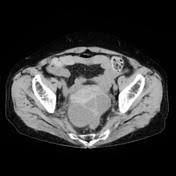

The Radiology Assistant Endometriosis Mri Detection from radiologyassistant.nl B, ct scan shows a nonspecific mass involving the right rectus muscle (arrow) subsequently proven to be endometriosis. After taking your medical and symptom history, and after performing a pelvic exam, your provider may recommend imaging. A ct or mri may show the endometriosis. Unusual sites of implantation and associated complications may make. Ct, endometriosis, female pelvis, mri, ultrasound. Endometriosis is a painful condition in which tissue that normally lines your uterus (endometrial tissue) grows in other parts of your pelvis, such as your ovaries or fallopian tubes. It can get worse before and during your period. An ultrasound, a ct scan, or an mri can make detailed pictures of your organs.

The new york endometriosis center which is one of the leading endometriosis treatment and gynecologic surgery centes in the world with offices in new york and greenwich. The ct and mr characteristics of abdominal wall endometriosis are nonspecific, both showing a solid enhancing mass in the abdominal wall. The most common sign of endometriosis is pain in your lower belly that doesn't go away. Endometriosis happens when the endometrium, tissue that usually lines the inside of your uterus, grows outside it. The most common symptom is pelvic pain. Endometriosis is a condition in which the inner lining of the uterus (endometrium) grows outside the uterus in locations such as the fallopian tubes, ovaries, bladder, or. Ct scans and the diagnosis of endometriosis ct scans can be used to visualize endometriosis in some areas of the abdomen, but are not very efficient in visualizing the pelvic organs, such as the uterus. The use of ultrasounds, magnetic resonance imaging (mri), computerized tomography (ct scan), and certain endometrial biopsy samples may be used as part of a diagnostic workup, but to date, anything less than surgical confirmation of endometriosis is considered uncertain. Tell the healthcare provider if you have ever had an allergic reaction to contrast liquid. It is a painful chronic disease that is estimated to affect 10% of women of all ages and backgrounds during their reproductive years. There are also no specific blood tests to diagnose endometriosis. Imaging exams, such as ultrasound, mri, or ct scans are used to take pictures of the inside of your body. An ultrasound, a ct scan, or an mri can make detailed pictures of your organs.

Treatment options include surgery and hormones. An ultrasound, a ct scan, or an mri can make detailed pictures of your organs. Unusual sites of implantation and associated complications may make. The most common symptom is pelvic pain. Reproductive medicine associates of connecticut with fertility clinics in connecticut and new york. Endometriosis is an important cause of chronic pelvic pain and infertility. Imaging exams, such as ultrasound, mri, or ct scans are used to take pictures of the inside of your body. A ct or mri may show the endometriosis. Learn about treatment, causes, stages, surgery, and diagnosis. Endometriosis is a painful condition in which tissue that normally lines your uterus (endometrial tissue) grows in other parts of your pelvis, such as your ovaries or fallopian tubes. Ct, endometriosis, female pelvis, mri, ultrasound. Endometriosis is an important gynecologic disorder primarily affecting women during their reproductive years. You may be given contrast liquid to help your abdomen show up better in the pictures.